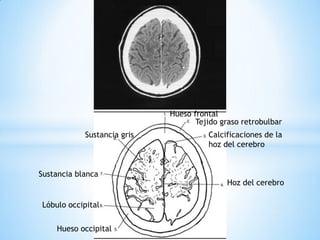

Hueso frontal

Tejido graso retrobulbar

Calcificaciones de la

hoz del cerebro

Hueso occipital

Sustancia blanca

Lóbulo occipital

Sustancia gris

Hueso frontal Tejidograso retrobulbar Calcificaciones de la hoz del cerebro Hoz del cerebro Hueso occipital Sustancia blanca Lóbulo occipital Sustancia gris

La hoz delcerebro Hueso parietal Hueso frontal Tejido graso retrobulbar Calcificaciones de la hoz cerebral